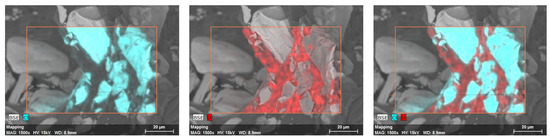

3.5. Microtomography